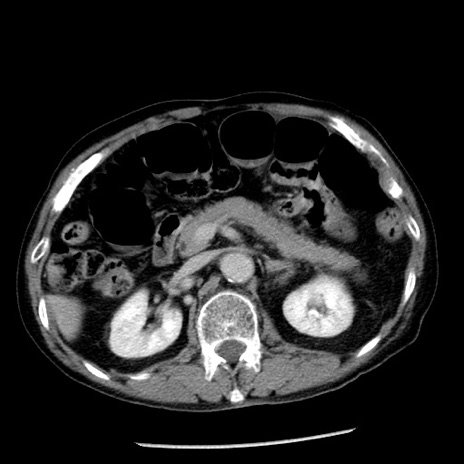

症例26(横断像)

冠状断像

【症例】80歳代男性

【主訴】嘔吐

【現病歴】昨晩2回嘔吐あり、今朝になっても嘔吐あり。来院。

【既往歴】胃潰瘍

【身体所見】意識清明、BT 37.6℃、BP 166/95mmHg、HR 100bpm、SpO2 97%、腹部:平坦・軟、腸蠕動音聴取良好、圧痛なし。

【データ】WBC 21900、CRP 1.46